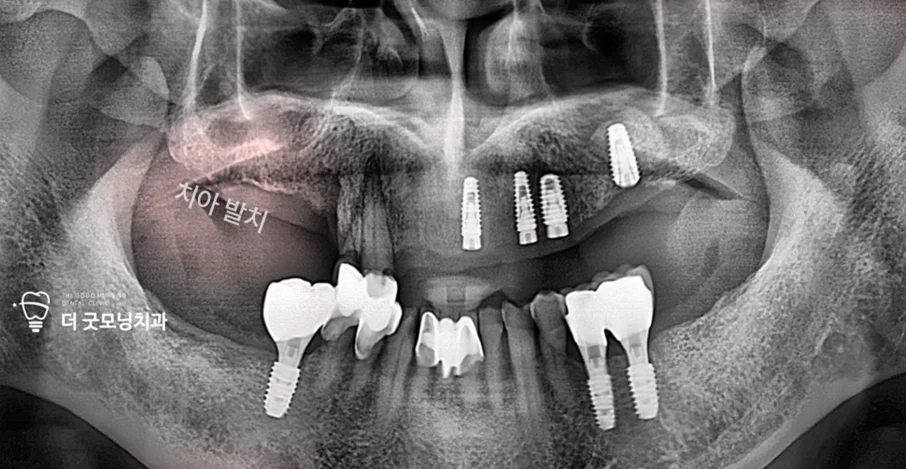

Step 2. 하악 치료 — 국민건강보험 임플란트 적용

해당 환자는 70대였으며, 잔존치가 있었기 때문에 국민건강보험 임플란트 혜택을 받을 수 있었습니다. 충치로 보존이 어렵던 하악 어금니 2개를 발치한 후, 건강보험 임플란트 2개와 비급여 임플란트 1개를 식립하여 하악 치료를 완료했습니다.

Step 4. 수면마취(의식하 진정) 하 좌측 수술

수술 전 맥박·호흡 등 생체징후 모니터링 장비를 세팅하고, 정맥 라인을 통해 약제를 천천히 투여하여 의식하 진정 상태에서 수술을 진행했습니다. 좌측 수술 시 상악동과의 거리가 가까워 상악동 거상술을 함께 시행하였으며, 4개 식립 중 3개를 사보험으로 처리했습니다.

Step 6. 추가 임플란트 식립 — 보험 적용 기간 분리 전략

1년이 경과하여 새로운 보험 적용 기간이 시작되었습니다. 좌측 임플란트의 유착을 확인한 후 로딩 작업을 완료하고, 우측에 4개의 임플란트를 추가 식립했습니다. 이번 수술도 수면마취(의식하 진정) 하에 진행되었습니다.